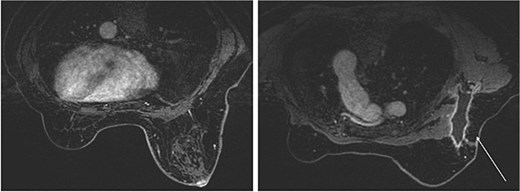

The mammography examination did not reveal any obvious abnormal findings in the right breast (Fig. 1). The breast ultrasound examination also did not reveal any obvious abnormal findings in the breast. The chest computed tomography examination revealed a lymph node that had enlarged to 46 × 34 mm in the right axilla (Fig. 2). There were no enlarged lymph nodes in the mediastinum, hilar region or supraclavicular fossa, and there were no signs of distant metastasis. Magnetic resonance imaging (MRI) of the breast showed no lesions in the right breast, and a lymph node 46 × 34 mm in size was found enlarged in the right axilla (Fig. 3).

Breast magnetic resonance imaging (MRI) findings. No lesions were observed in the right breast, and a lymph node enlarged to 46 × 34 mm was observed in the right axilla.